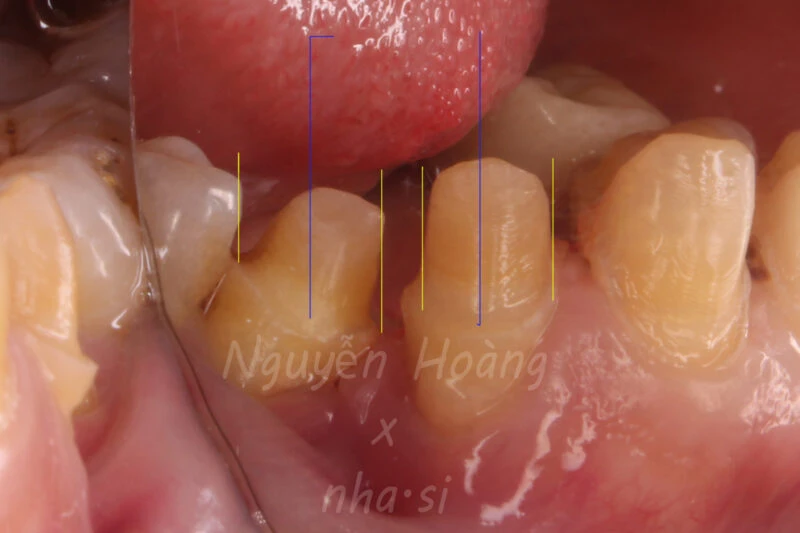

Hình 1: Hàm dưới trước khi phục hình

Hình 3: Hướng lắp phục hình được thể hiện bằng đường kẻ màu xanh. Hướng thành trục của cùi cần mài được thể hiện bằng đường kẻ màu vàng.